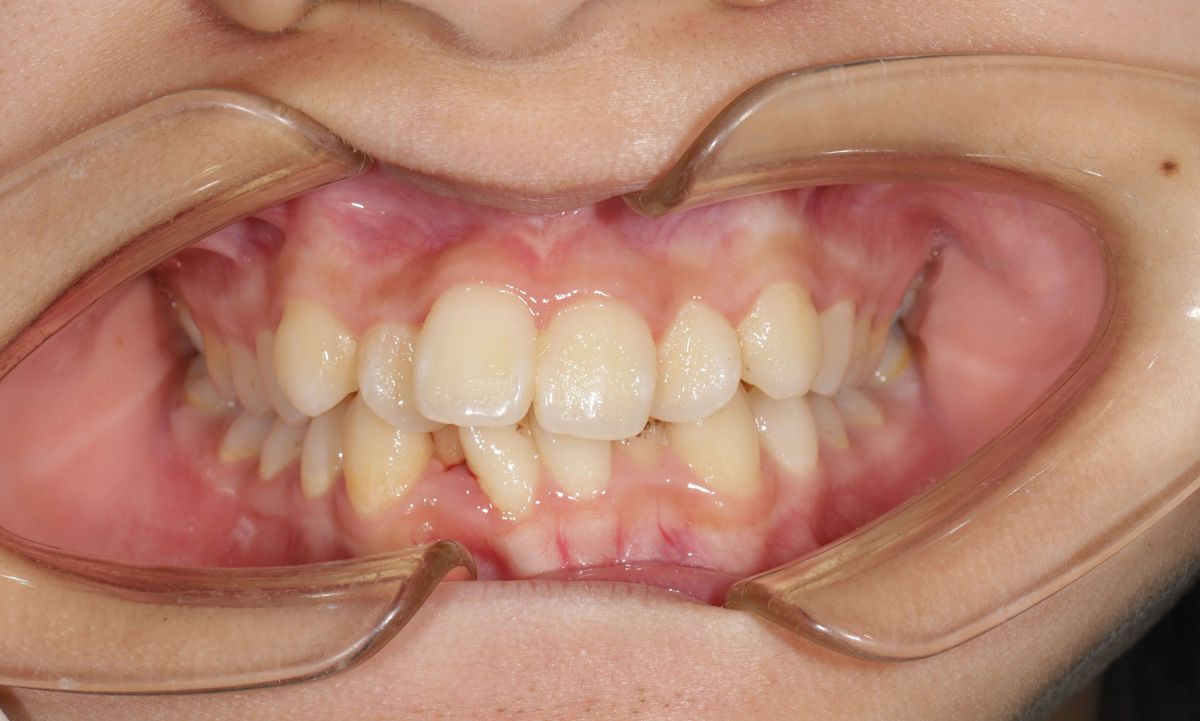

1 Tình trạng trước niềng răng

Sau khi thăm khám tại Nha khoa Hanseoul, bác sĩ ghi nhận các vấn đề:- Răng lệch lạc, chen chúc nghiêm trọng cả hai hàm

- Không đủ khoảng sắp xếp răng

- Khớp cắn sai (cắn chìa – cắn sâu)

- Ảnh hưởng thẩm mỹ khuôn mặt và chức năng ăn nhai